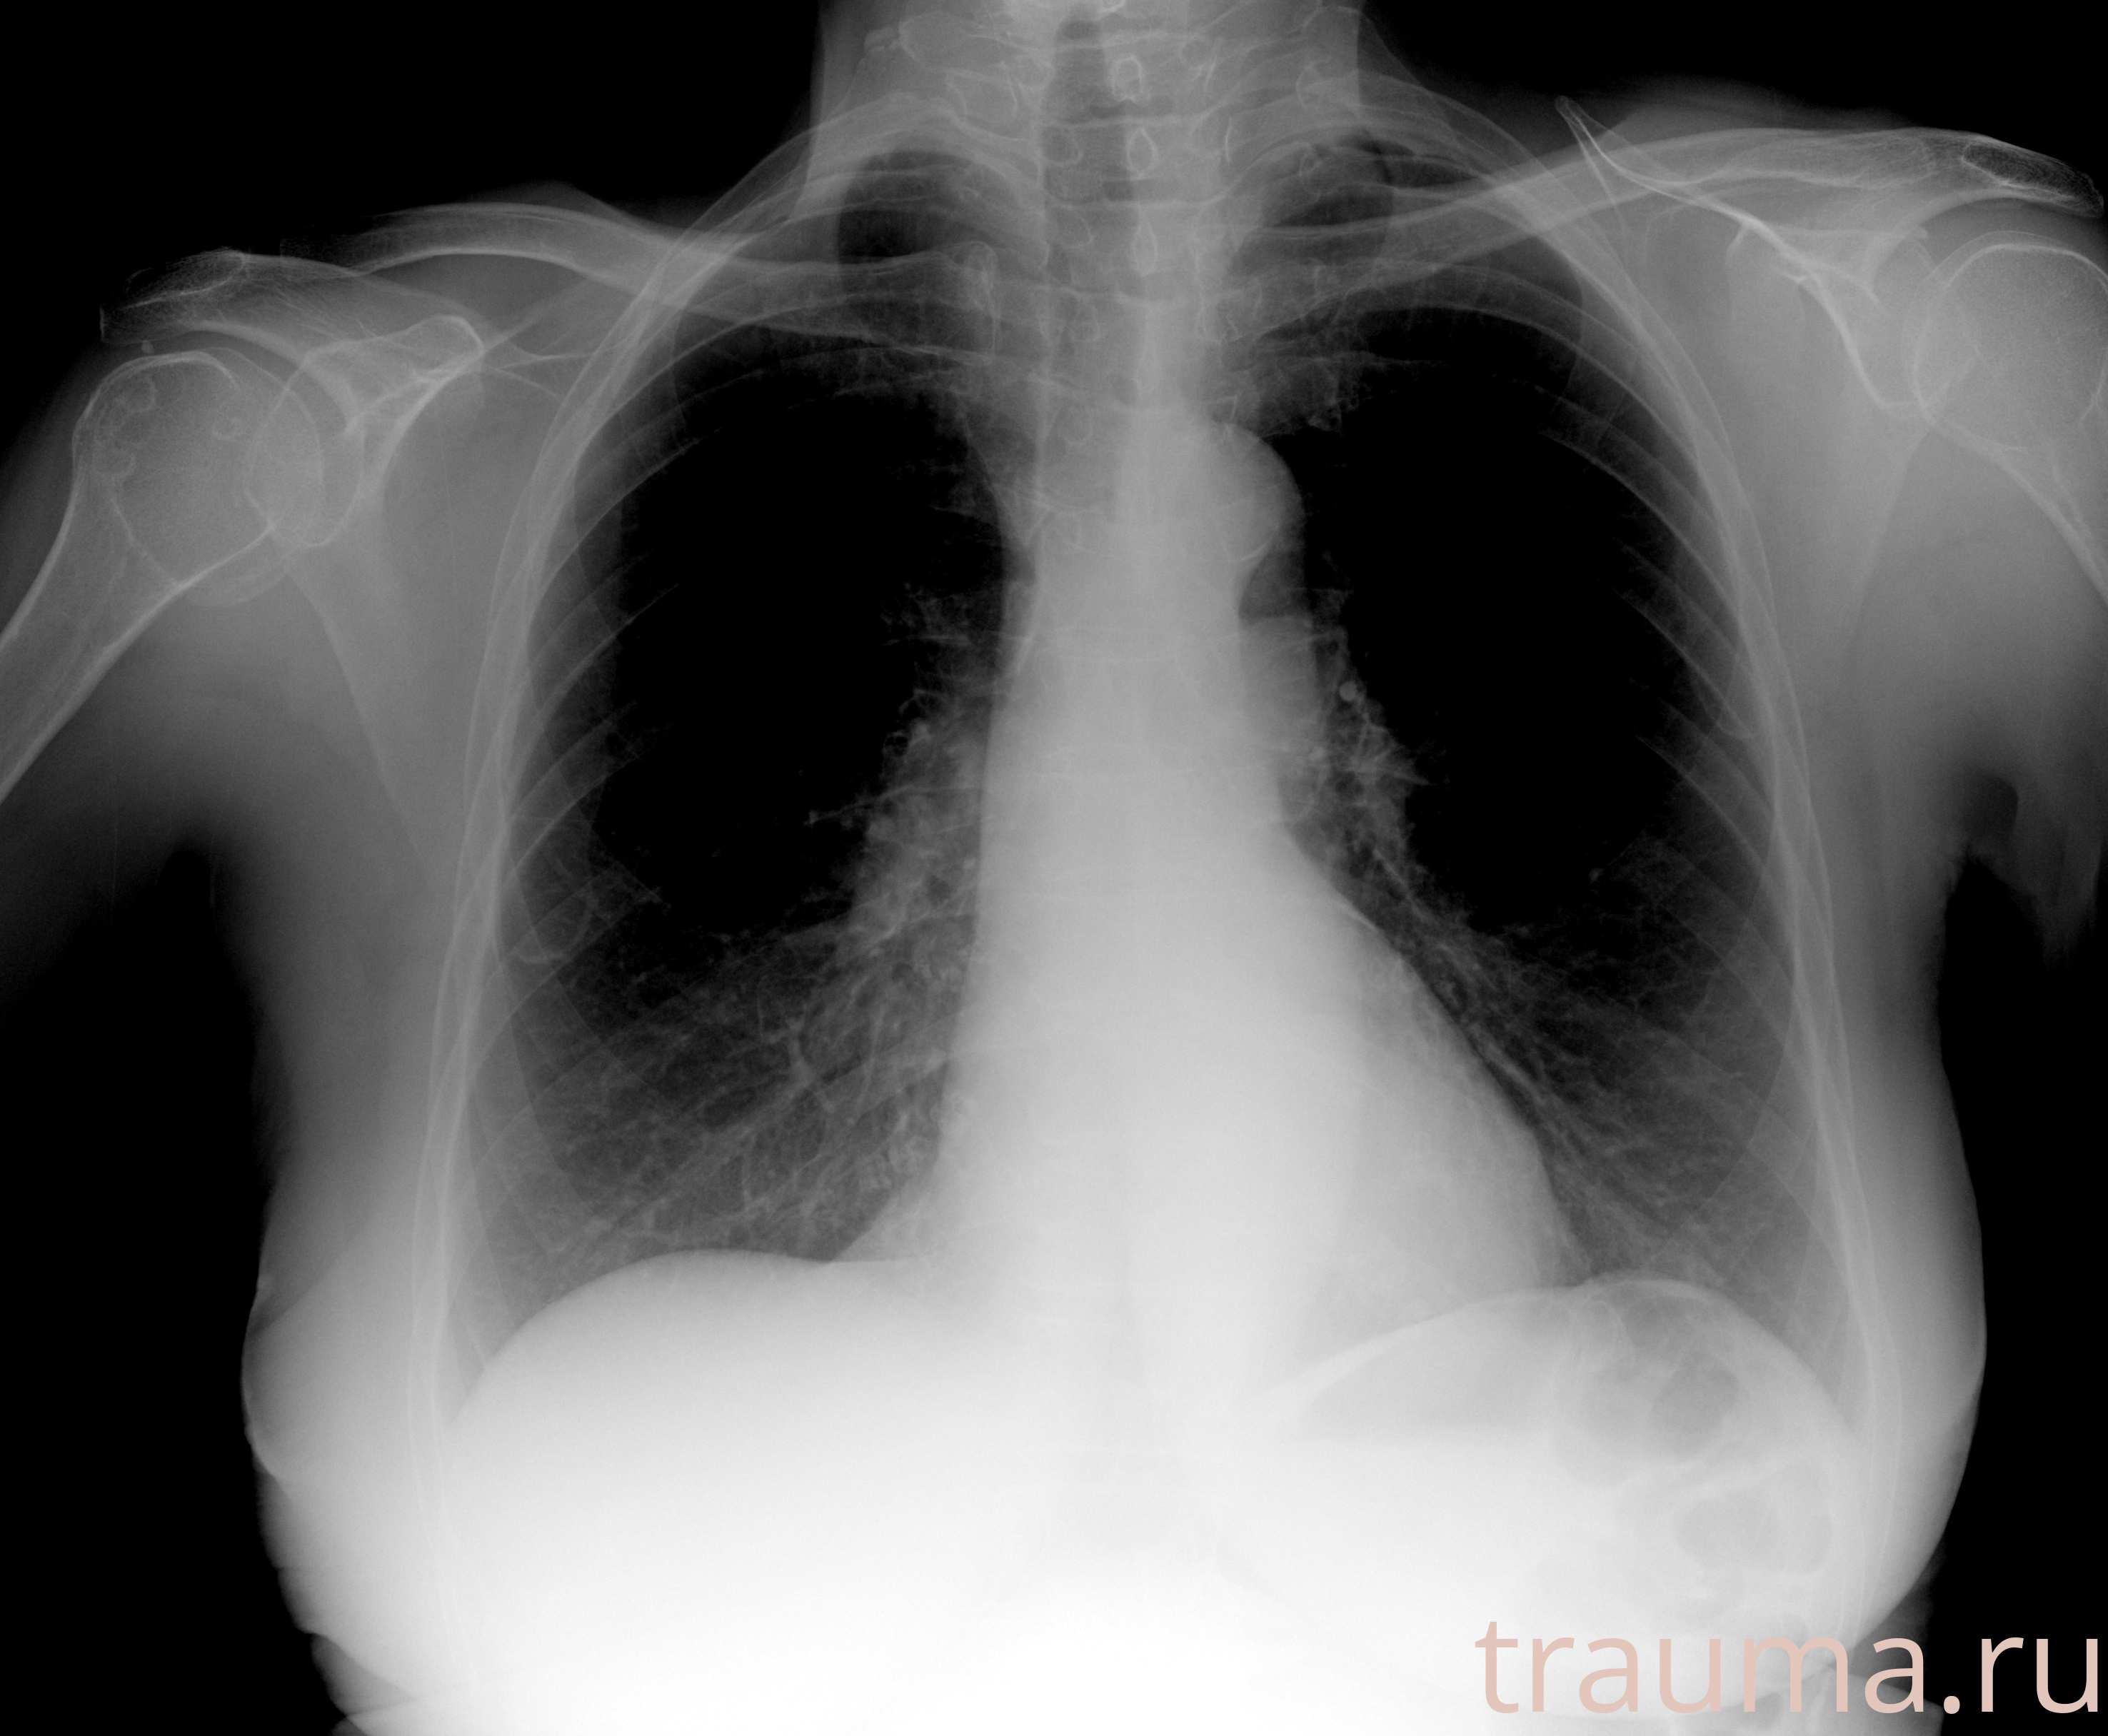

Рентген на дому: по вашему адресу приезжает врач-рентгенолог, травматолог-ортопед с мобильным рентгеновским аппаратом, проводит диагностику травмы или заболевания, делает необходимые рентгенограммы, дает рекомендации по дальнейшему лечению. Получить качественные снимки в домашних условиях возможно благодаря уникальной методике, разработанной МосРентген Центром для института  Склифосовского

при переломе шейки бедра и пневмонии от компании МосРентген Центр - партнера Института имени Склифосовского